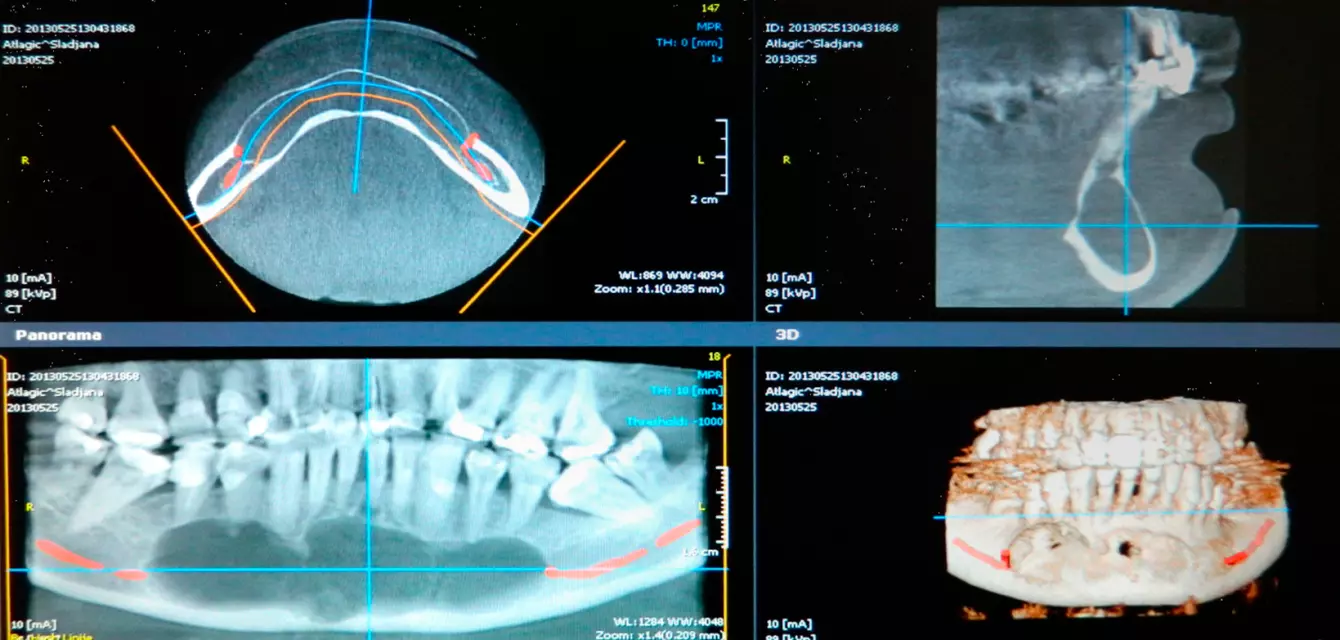

Posedujemo moderno opremljen prostor sa 2 operacione sale za oralnu, parodontalnu, maksilofacijalnu hirurgiju i implantologiju, rendgen kabinet, prostor za pripremu i sterilizaciju instrumenata, kao i čekaonica za pacijente. Istakli smo po najboljim zubnim implantatima u gradu.